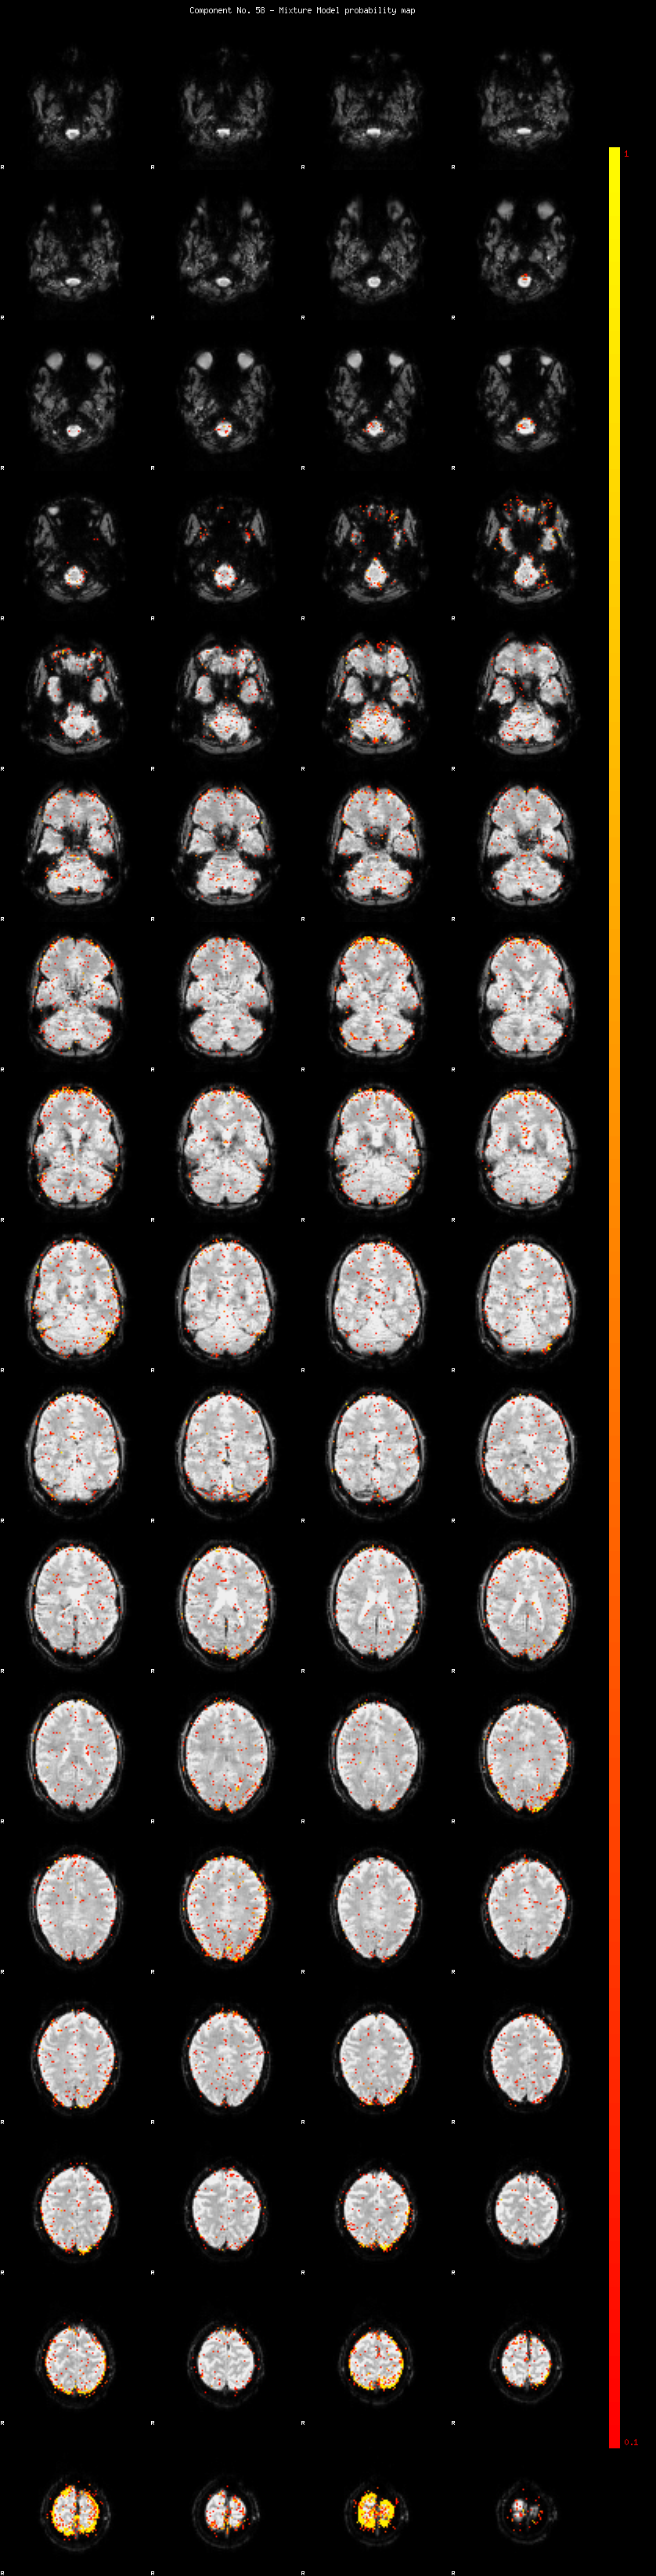

IC_58 Mixture Model fit

Means : 0.000000 2.705990 -2.751573

Vars : 1.000000 2.878072 0.715754

Prop. : 0.970949 0.020324 0.008726